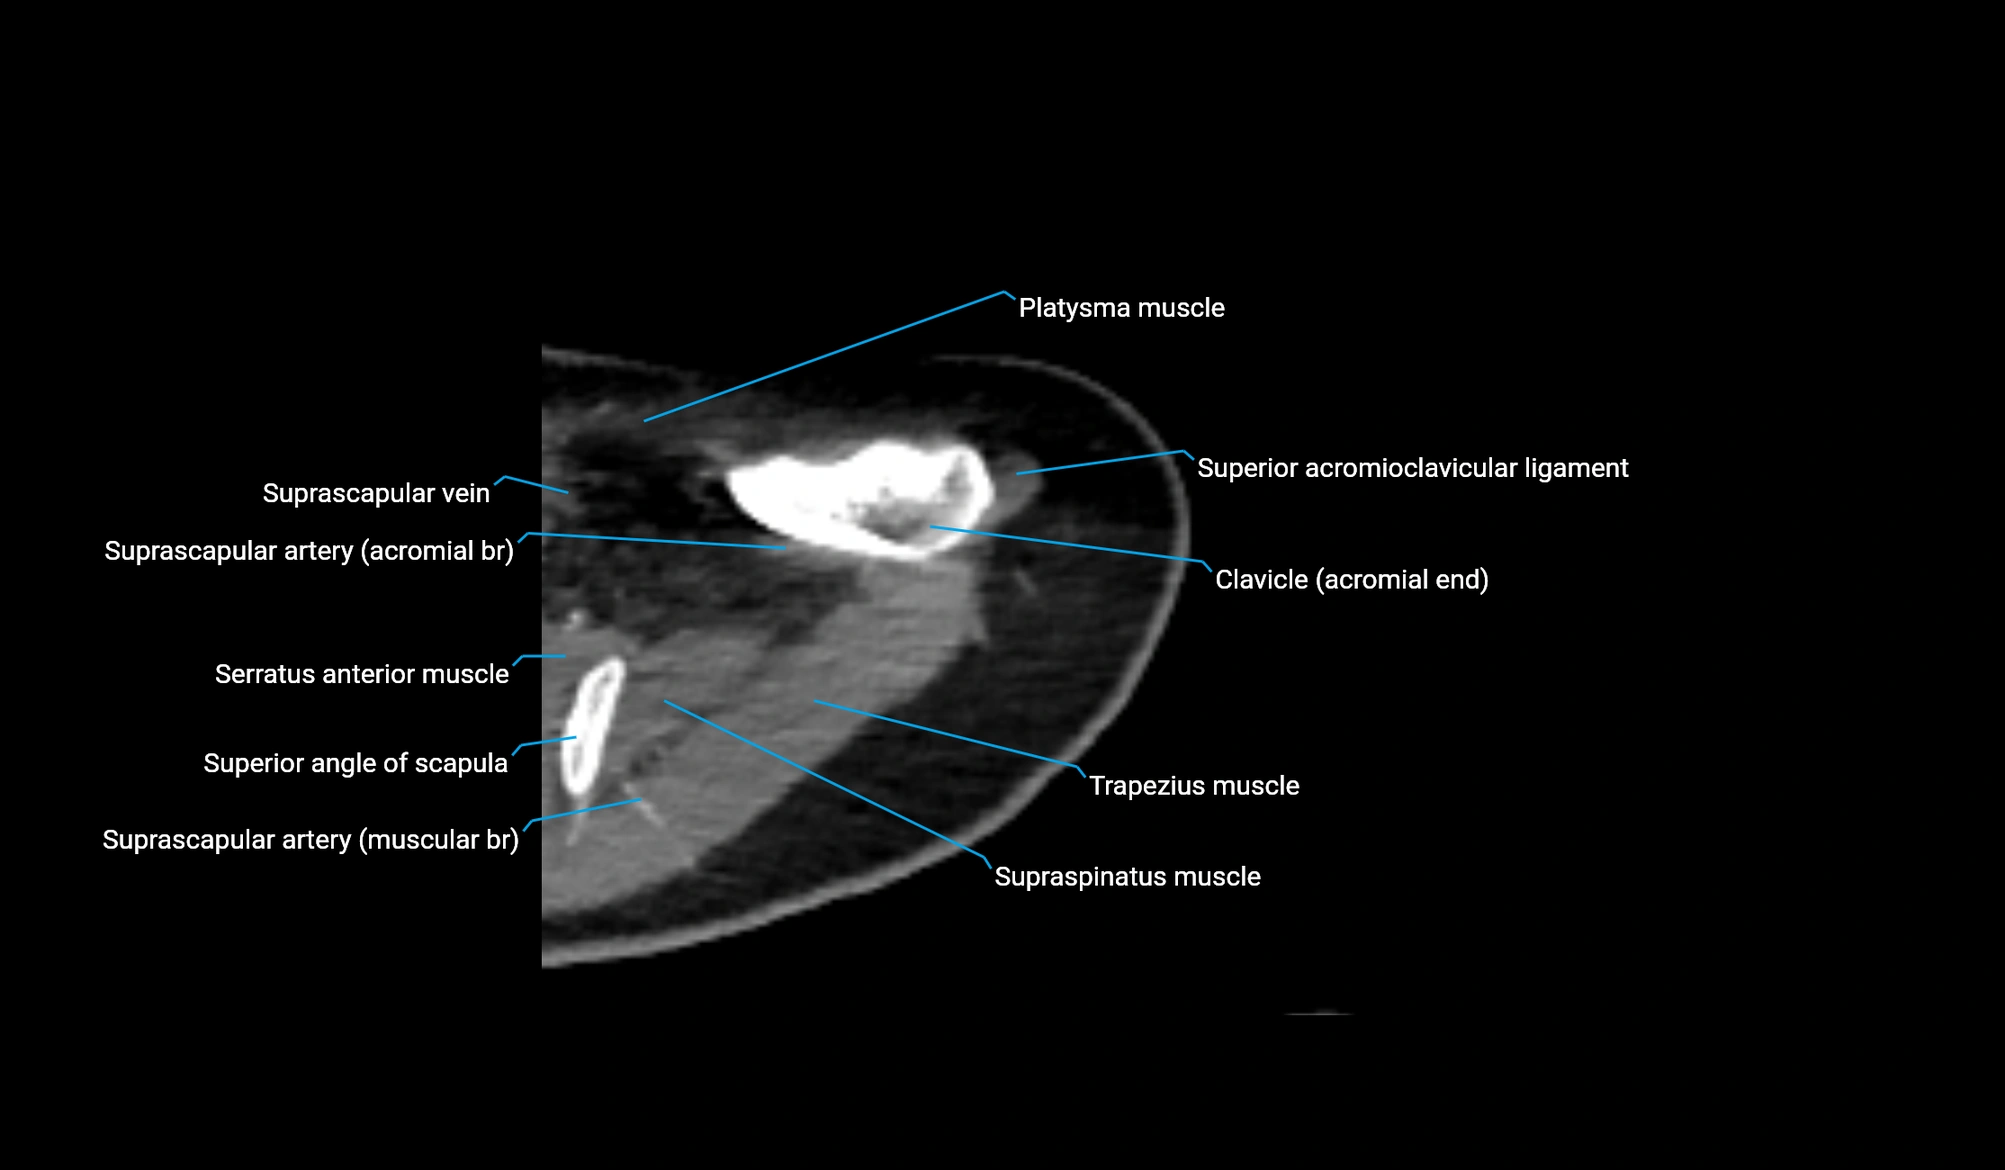

- Acromial end of clavicle

- Acromioclavicular ligament

- Acromion process of scapula

- Superior acromioclavicular ligament

- Superior angle of scapula

- Subclavius muscle

- Supraspinatus muscle

- Spine of scapula